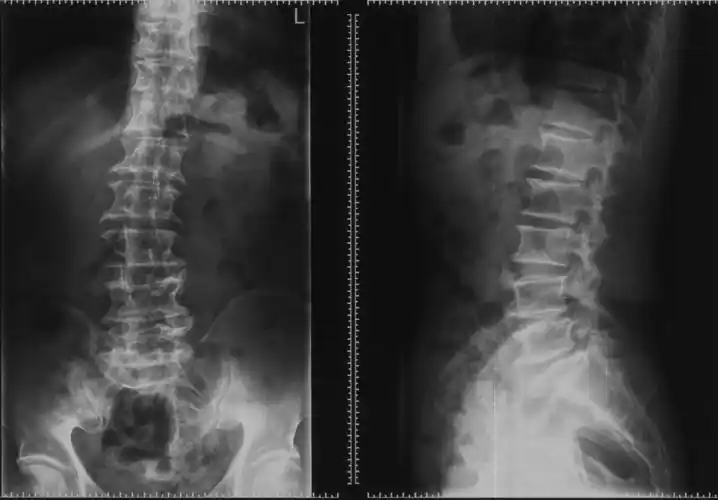

25床 王红芝 l5/s1椎间盘突出